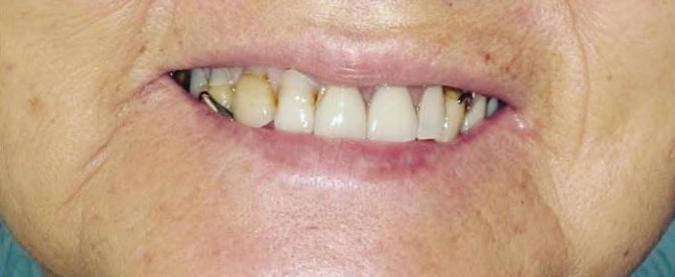

Can just four implants replace all of the teeth on the top or the bottom of your mouth? Thanks to advances in dental implant technology, that answer is a resounding yes.

Tooth loss is extremely common among adults, especially as we age. Rather than living with the discomfort and hassles of dentures, many people are opting for what is called “all-onfour” dental implant restoration.

screw that fits inside your jawbone and replaces the root-part of a missing tooth. Minor surgery is required to insert the implants. Once the implant is in place, a crown is attached to give you a highly realistic-looking and functional prosthetic tooth.

You do not need a dental implant for each and every one of your missing teeth. All you need is four precisely placed implants on the top of your mouth, and four on the bottom, to restore your full smile. That’s the beauty of the all-on-four. And because the implant is made of titanium, it has the unique ability to fuse to living bone and function as part of it. So eventually, the dental implant becomes part of the jawbone and serves as a strong, longlasting foundation for your new teeth.

Besides ensuring that your implants are permanently fixed in place, this bone fusion has another important benefit: it prevents future bone loss in the jaw. This helps to maintain a more youthful facial structure – and better

Please see “All-On-Four,” page 62